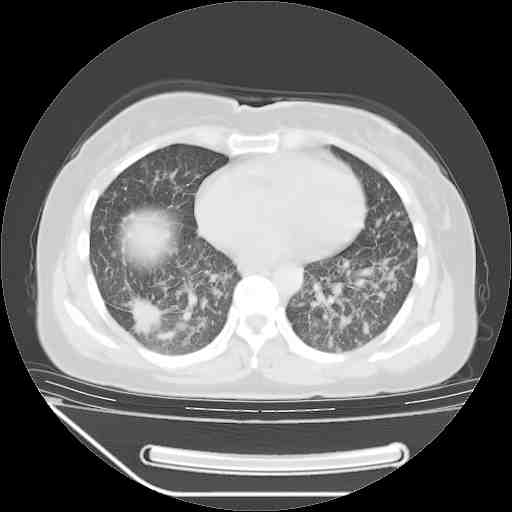

考虑  腺癌肺内转移,治疗较前病灶缩小、减少

支持肺癌并肺内淋巴管炎,  原发灶小了,但转移较前片明显了.

支持右肺下叶周围型肺癌并肺内淋巴管炎,  原发灶小了,但转移较前片明显了.。

标准的细支气管肺泡癌呀!治疗后病情有所控制,也没治愈的迹象!

支持右肺下叶周围型肺癌并肺内淋巴管炎;病灶有所控制。

支持右肺下叶周围型肺癌并肺内淋巴管炎,  原发灶小了,但转移较前片明显了.